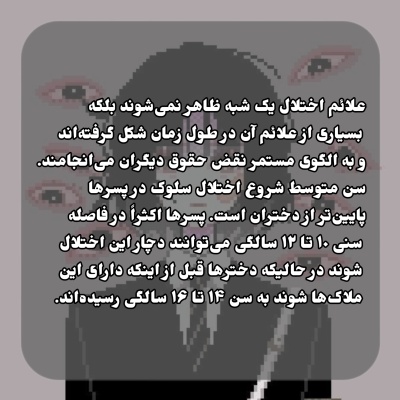

معرفی اختلال سلوک؛ اختلالی در رابطه با رفتار پرخاشگرانه کودکان و نوجوانان.